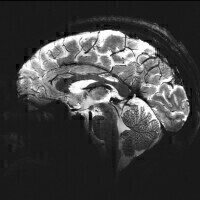

One of the first 11.7T images of the human brain recently acquired on a similar scanner at Neurospin in Paris. It has an in-plane resolution of just 200 microns. (Credit: University of Nottingham)

Ultra-high field MRI offers huge benefits in terms of improved sensitivity which will enable higher spatial resolution imaging, faster imaging, and greater sensitivity to physiological changes. The scanner will also provide a step change in the capabilities of magnetic resonance spectroscopy (MRS) to provide information about the biochemistry of the human body.